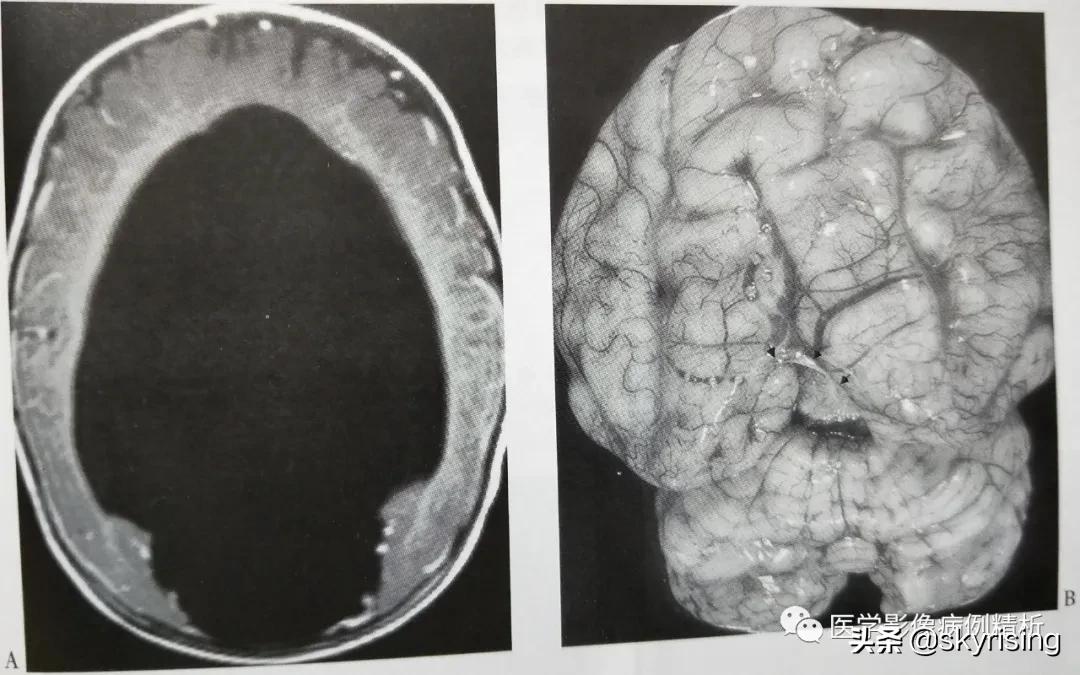

MR影像表现:双侧大脑半球完全融合,或仅表现一个团块状软组织。半球间裂和大脑镰缺如,无胼胝体,仅表现一个未发育的胼胝板。巨大全脑室,无透明隔。如下图所示。右侧尸体标本可见脑组织呈团块软组织改变。

本型是前脑无裂畸形中发育最好、畸形最少的一个分型。双侧额叶靠近胼胝体嘴部和体前部部分实质融合,大脑前纵裂几乎完全存在,大脑镰发育不全,胼胝体前部发育不良,透明隔缺如,侧脑室额角发育正常或轻微变异,大脑后纵裂显示正常。如下图所示,双侧额叶部分脑实质融合,双侧额角略纤细,形态尚正常,注意短箭头所示大脑前动脉走行于前缘,本例偏于脑叶型和半脑叶型中间状态。